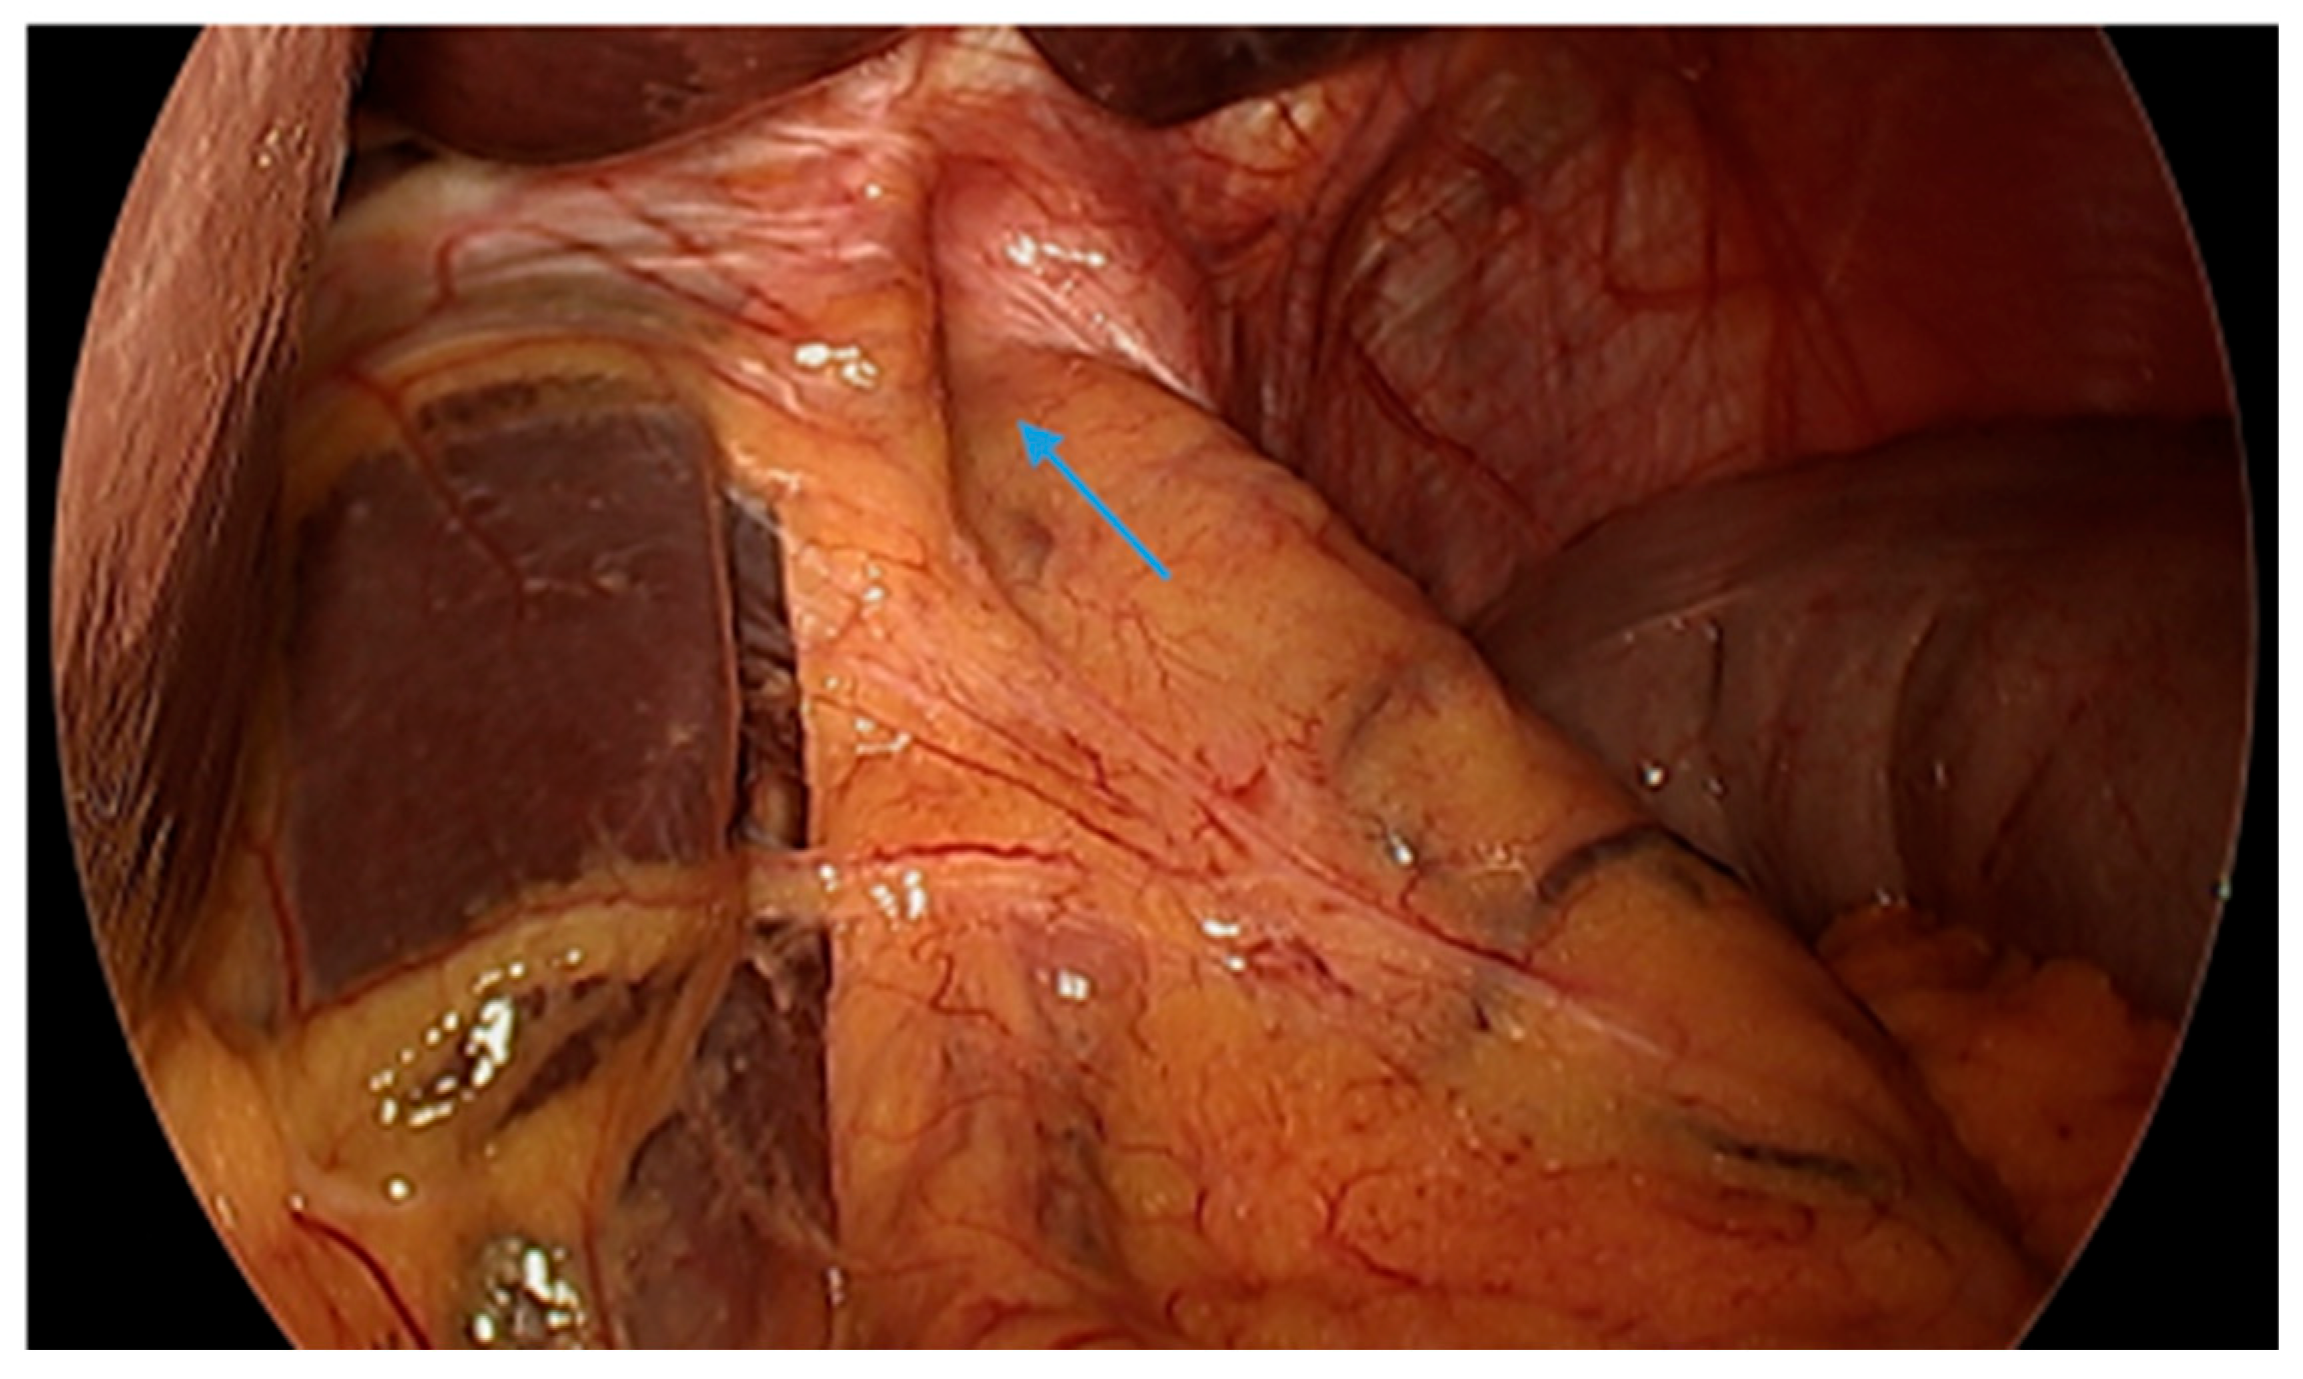

Figure 10.

Laparoscopic image demonstrates hiatal hernia repair and successful placement of a magnetic sphincter augmentation device (arrow) around the esophagus in a patient post-sleeve gastrectomy with gastroesophageal reflux disease. Image courtesy of Dr. Brian Louie, Chief of Thoracic Surgery at Swedish Medical Center in Seattle, Washington, USA.